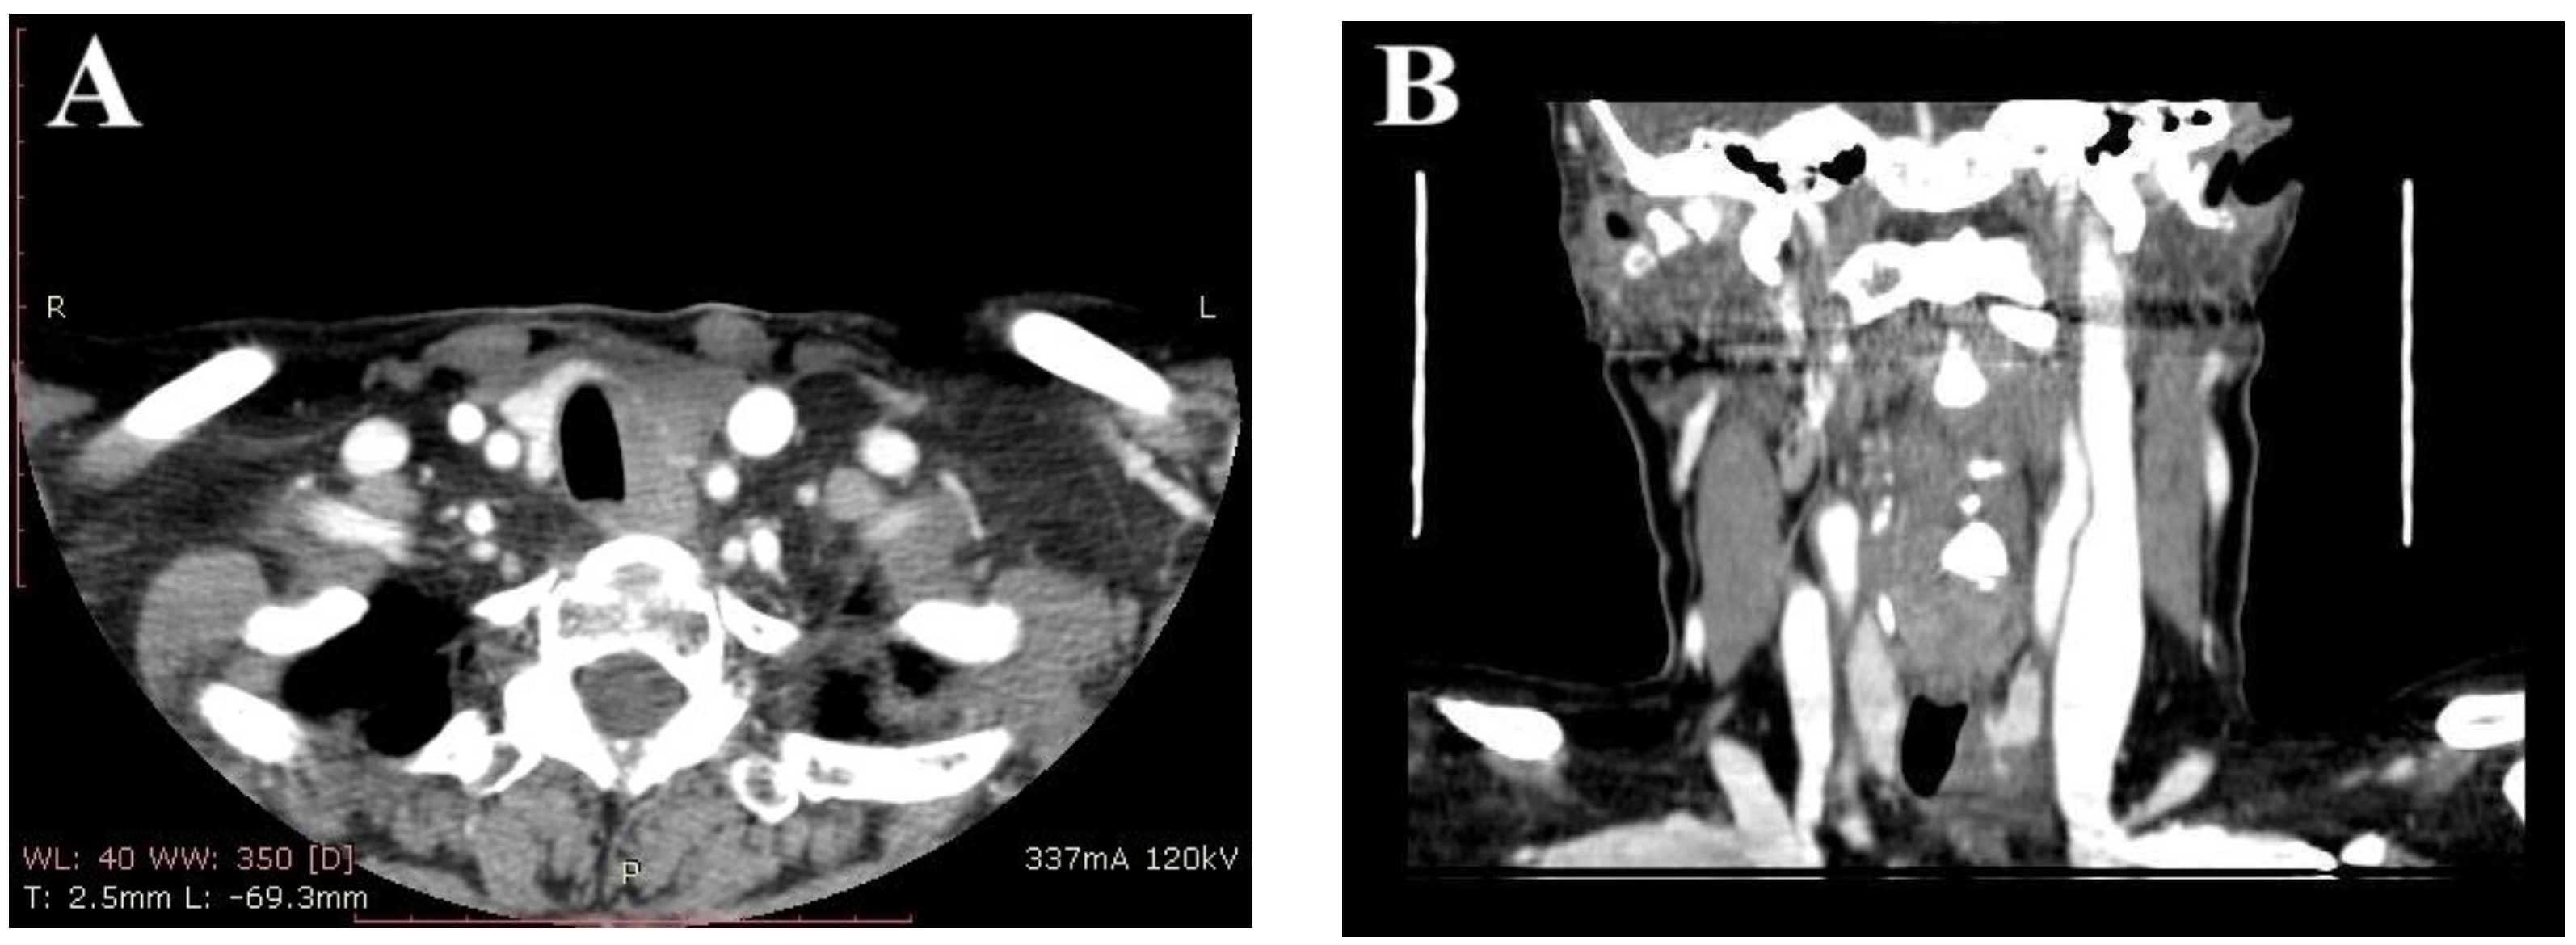

2. Case Report